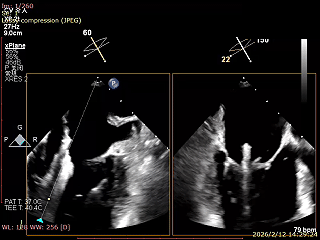

术前食道超声评估

三尖瓣关闭不全重度(4+,平均缩流颈10mm),反流口以前隔、中央为主,部分后隔,瓣叶未见明显脱垂及GAP,三尖瓣环扩张(瓣环平均径43mm),二尖瓣中-重度反流,肺动脉高压(PASP:44mmHg)。